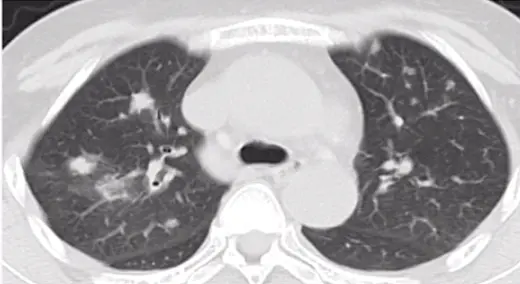

第五题:如下图所示,病变表现为大小不等的肺结节,结节周围有晕征,结节内有空洞。

第五题答案:侵袭性肺曲霉病,曲霉侵犯血管后出血会造成晕征。